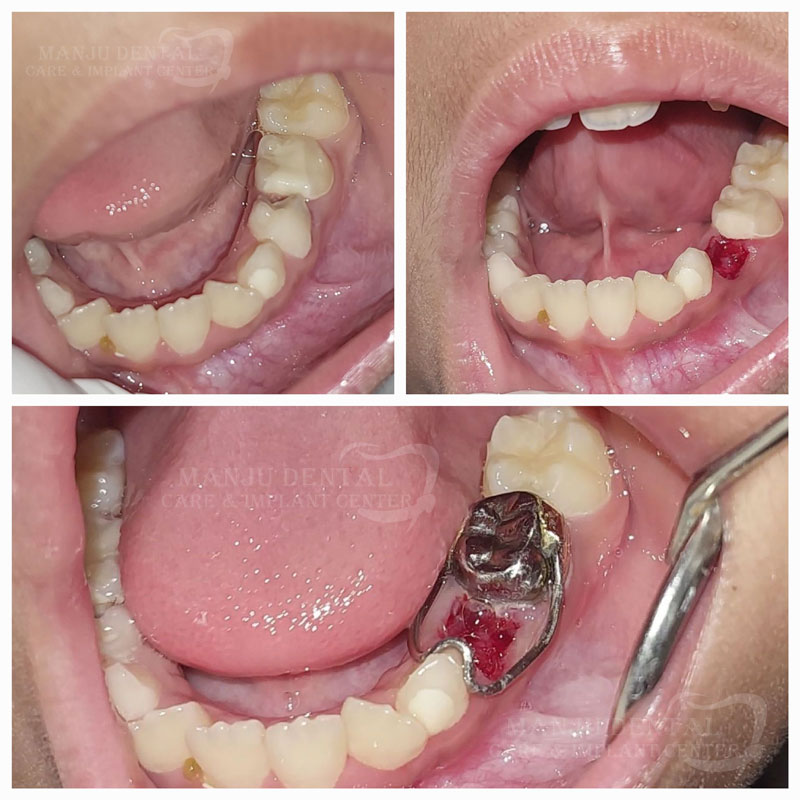

Early Intervention For Neonatal Tooth to Avoid Aspiration And Ensure Smooth Feeding and Oral Health

Space Maintainer Guiding Eruption For a Perfect Future Smile

Pulpectomy of Primary Teeth Keeping It Strong Till Its Time To Go